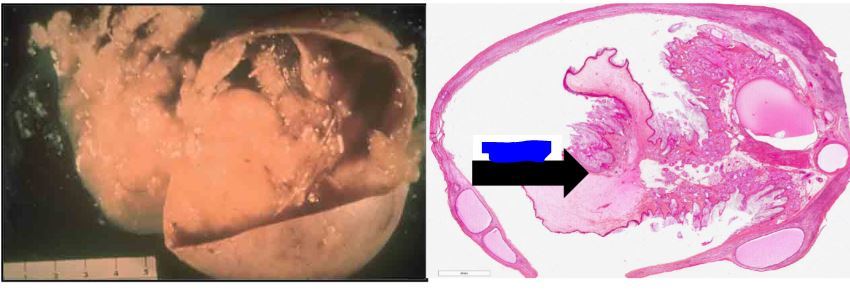

tératome bénin de l’ovaire

fleche = polype

on voit des kystes dans l’ovaire

o=ovaire

k=intra kystique

p= polype

interieur d’un polype avec follicule pileux et vrai peau